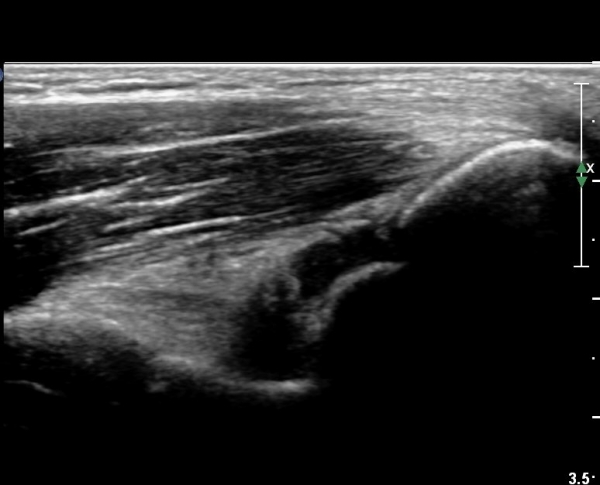

ÆÈ²ÞÄ¡ ¾ÕÂÊ ¿ÜÃø, ¼ÒµÎ(capitulum) Á¾´Ü¸é°Ë»ç¿¡¼­ ¼ÒµÎ Àü¸éºÎ¿Í ¿ä°ñµÎ Àü¸é¿¡ ¼ö¾×Àú·ù°¡ °üÂûµÊ(»çÁø 3, 4).

¼ÒµÎ Ⱦ´Ü¸é°Ë»ç¿¡¼­µµ ¼ÒµÎ Àü¸é¿¡ ¼ö¾×Àú·ù°¡ °üÂûµÊ(»çÁø 5).